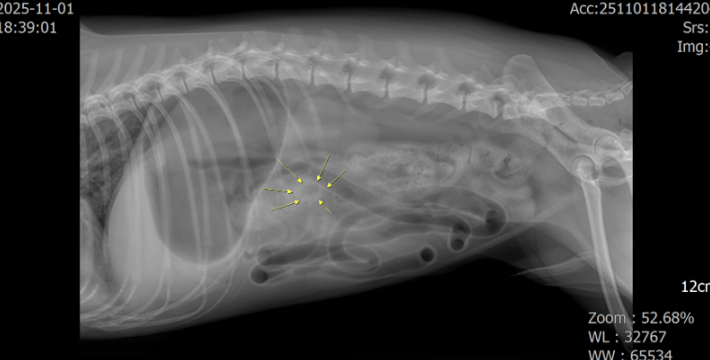

X-ray

소장의 이물 음영이 보이고 mechanical obstruction으로 인해 소장의 가스음영이 관찰되었고 더 명확히 이물의 존재 확인을 위해 초음파 검사가 진행되었습니다.